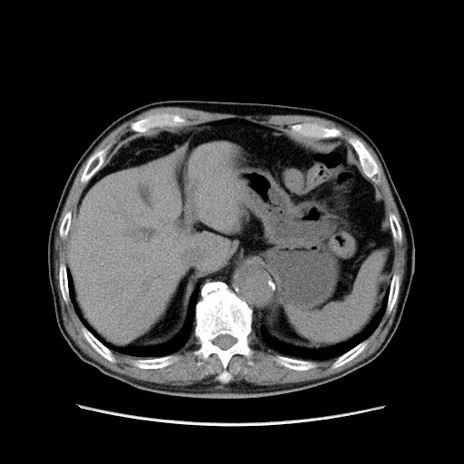

症例24(横断像)

【症例】80歳代男性

【主訴】左側腹部痛、嘔吐

【現病歴】本日早朝より左腹部に痛みあり。昼頃嘔吐認めたため、救急要請。

【既往歴】直腸癌(Mile手術)、胆摘

【身体所見】意識清明、BT 35.9℃、BP 221/93mmHg、SpO2 97%(RA) 、腹部:左ストーマ周囲に限局性の腹部膨隆あり。 膨隆部自発痛・圧痛あり・軟。

【データ】WBC 7700、CRP 0.09